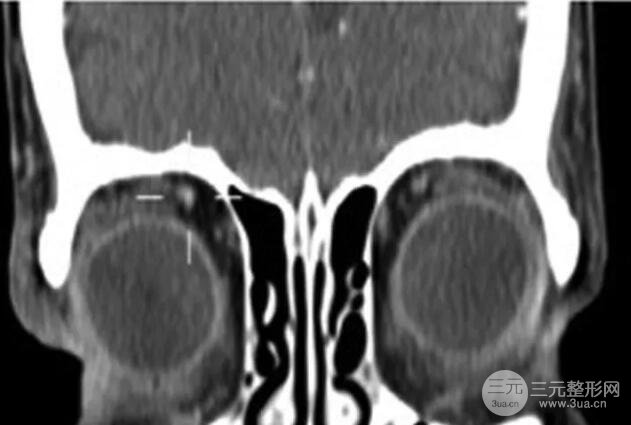

眼眶CT扫描发现前上眼眶和上睑皮下组织内有一个平的、放射不透明的眼眶肿块(见下图)